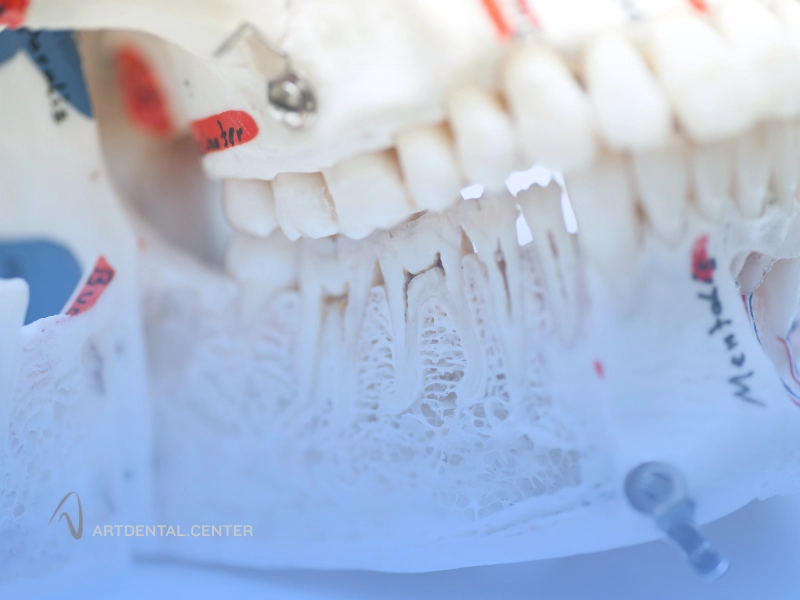

پیوند استخوان فک

پیوند استخوان کف لگن برای فک

پیوند استخوان فک چیست؟

پیوند استخوان فک یا Bone Grafting فرآیندی است که طی آن حجم استخوان فک افزایش می‌یابد تا امکان کاشت ایمپلنت دندان فراهم شود. این روش می‌تواند در مواردی مانند تحلیل استخوان به دلیل کشیدن دندان، بیماری‌های لثه، آسیب‌های فیزیکی یا سن بالا ضروری باشد. در این فرایند، مواد استخوانی از منابع مختلف استفاده می‌شوند، از جمله:

• استخوان خود بیمار (Autograft)

• استخوان اهدا شده از فرد دیگر (Allograft)

• استخوان مصنوعی یا بیولوژیکی (Alloplast یا Xenograft)

مراحل پیوند استخوان فک

• معاینه و تصویربرداری: با استفاده از سی‌تی اسکن یا رادیوگرافی سه‌بعدی، حجم استخوان فک ارزیابی می‌شود.

• انتخاب نوع پیوند: بسته به نیاز بیمار، نوع استخوان (خود فرد، اهدا شده یا مصنوعی) انتخاب می‌شود.

• عمل جراحی پیوند: استخوان انتخاب شده به ناحیه مورد نظر اضافه می‌شود و در صورت نیاز با مواد تثبیت‌کننده محکم می‌گردد.

• بهبودی و رشد استخوان: طی چند ماه، استخوان پیوند شده با استخوان طبیعی ادغام شده و پایه‌ای محکم برای ایمپلنت ایجاد می‌کند.